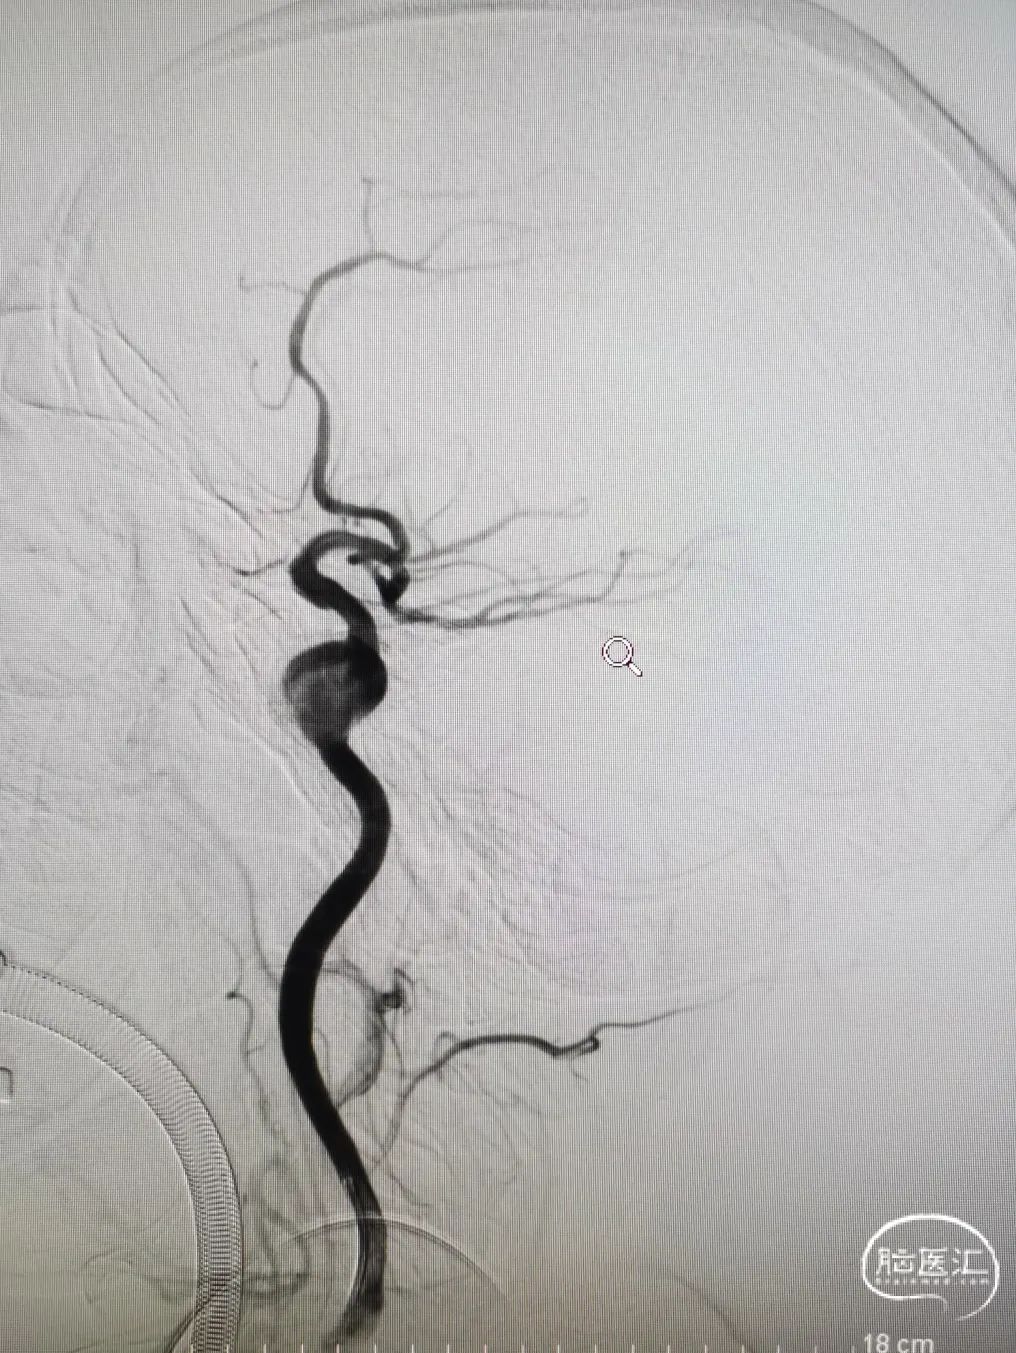

造影提示主动脉弓开口尚可,但颈动脉迂曲明显。

前交通囊状动脉瘤约4mm╳3mm,瘤颈约4mm。

右颈内动脉交通段以远瘤样扩张,载瘤动脉完全瘤化,局部可见多处小阜突起,无明显瘤颈,最大约16mm╳11mm。

右侧后交通动脉自瘤体远端发出。

右侧大脑中动脉直径约3mm,颈内动脉海绵窦段约4.5mm。

图4